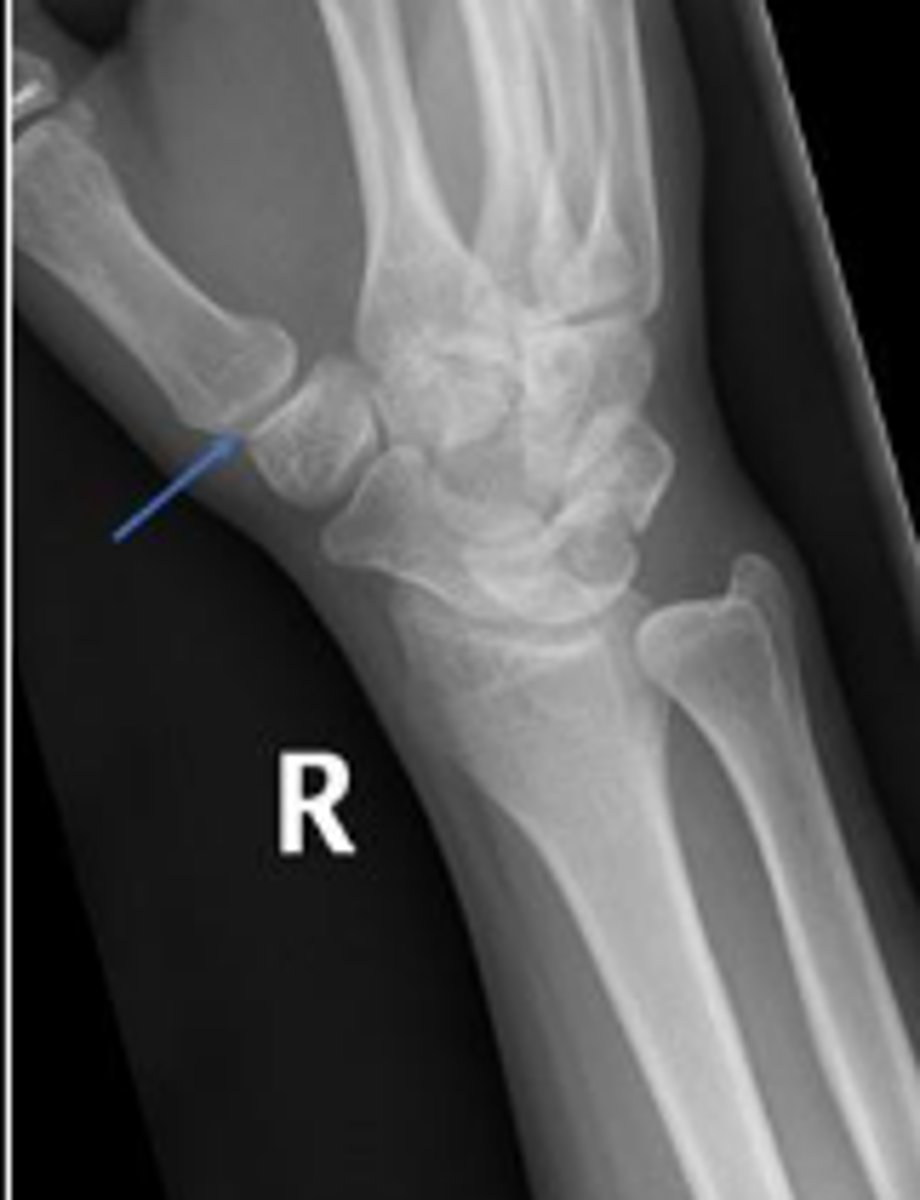

Medial oblique of the right wrist

What is the name of the radiographic view?

Right scaphoid

What is outlined?

What is the arrow pointing to?